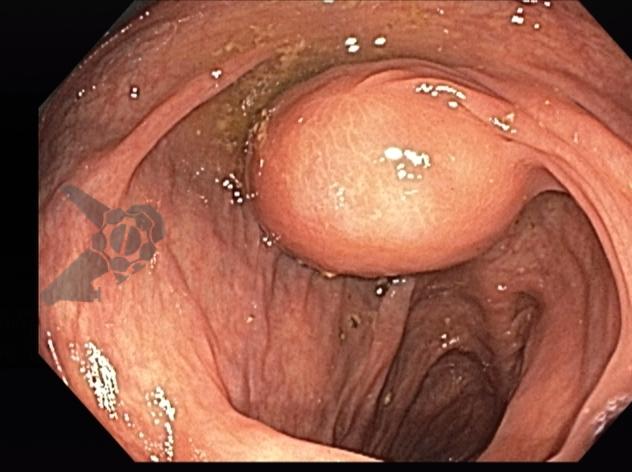

L.R.S., masculino, 8 meses, nascido a termo, com diagnóstico pré-natal de atresia de esôfago com fístula traqueoesofágica distal (Vogt IIIb/Gross C), submetido à correção cirúrgica no 3º dia de vida. Aos 3 meses, passou a apresentar episódios recorrentes de tosse durante a alimentação, engasgos, regurgitação e perda de peso progressiva. A mãe relatou dificuldade em introduzir alimentos sólidos e episódios recorrentes de infecção respiratória nos últimos dois meses. Solicitada endoscopia digestiva alta, que evidenciou estenose puntiforme da anastomose esofágica. Iniciada terapia endoscópica com dilatação esofágica utilizando vela de Savary-Gilliard. Foram realizadas 4 sessões com intervalo de 2 semanas, com melhora progressiva da aceitação alimentar e ganho ponderal adequado. Após a 4ª dilatação, o paciente encontra-se em boa evolução clínica, com alimentação por via oral plena, sem episódios de engasgos ou perda ponderal.

O diagnóstico deve ser suspeitado diante de sinais e sintomas como perda ponderal, disfagia, engasgos e infecções respiratórias recorrentes, vindo a ser confirmado através da endoscopia digestiva alta [11].

O tratamento inicial a ser considerado é a dilatação endoscópica, seja com o balão hidrostático ou com a vela de Savary – Gilliard, não havendo diferença nos desfechos, de acordo com a literatura atual, entre as duas técnicas [12]. Entretanto, alguns trabalhos sugerem que a dilatação com balão pode apresentar menor risco de complicações[12,13,14]. Estudos mostram uma média de três sessões de dilatação para a resolução do quadro, sendo estas intervaladas em um período de duas a quatro semanas, a depender da sintomatologia e evolução clínica do paciente, sendo o ganho ponderal um dos fatores clínicos mais importantes a serem considerados [8,13].